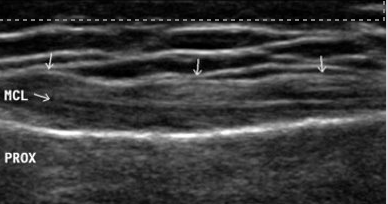

ligaments connect

bone to bone

ligaments are ____ and ________

thin

superficial

measurement and echogenicity of ligament

2-3mm

hypoechoic band

similar appearance to tendons

sonography techniques fro ligaments

stand off pad

long imaging only

Ligament